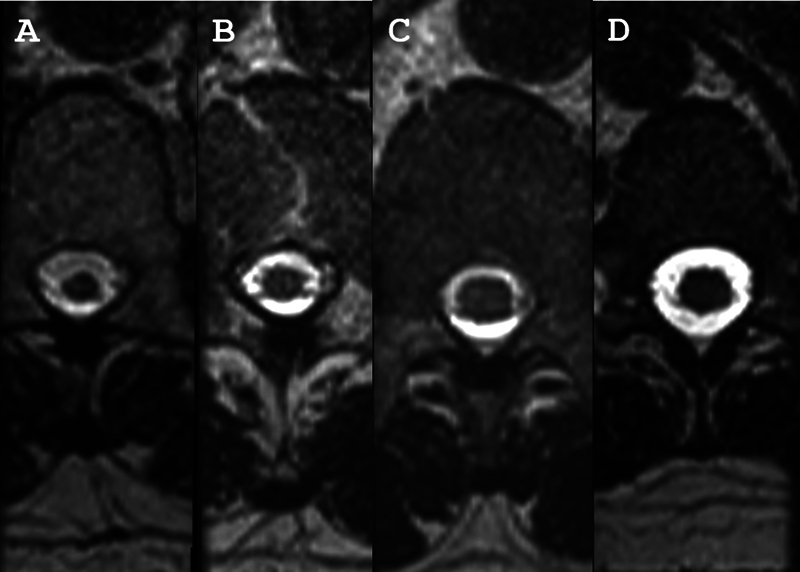

人类嗜t淋巴病毒1 (HTLV-1)相关脊髓病(HAM)的主要神经系统表现为痉挛性截瘫,但仅发生在5%的患者中。相比之下,约40%的htlv -1感染者出现泌尿系统功能障碍的症状,包括夜尿症、尿急和尿失禁,并可能发展为无法排尿。由于这些患者没有出现运动功能障碍,他们被归类为可能的HAM。胸椎脊髓(SC)萎缩是确诊性HAM患者磁共振成像(MRI)扫描中发现的主要异常,但在疑似HAM患者中尚未见SC损伤的报道。为了确定,通过对常规MRI指标的评估,我们可以检测到疑似HAM患者SC面积的减少。通过Western blot诊断HTLV-1感染,并使用1.5 t扫描仪进行MRI扫描。当SC面积小于鞘内面积的25%时考虑萎缩。我们观察到HTLV-1携带者、疑似和确诊HAM患者中SC区域的所有节段逐渐减少。值得注意的是,48.3%的疑似HAM患者表现为腰椎萎缩。使用MRI指标,本研究显示,在出现HTLV-1相关泌尿系统症状但无运动功能障碍的患者中,SC区腰椎节段萎缩。

The main neurologic manifestation of definitive human T-lymphotropic virus 1 (HTLV-1)-associated myelopathy (HAM) is spastic paraparesis, but it only occurs in 5% of the patients. In contrast, about 40% of HTLV-1-infected subjects present symptoms of urologic dysfunction, including nocturia, urgency, and incontinence, which may progress to an inability to void urine. As these patients do not present motor dysfunction, they are classified as probable HAM. Atrophy of the thoracic spinal cord (SC) is the main abnormality found on magnetic resonance image (MRI) scans of patients with definitive HAM, but damage to the SC has not been reported in patients with probable HAM.To determine if, through an evaluation of the metrics of conventional MRI, we can detect a decrease in the area of the SC in patients with probable HAM.Infection by HTLV-1 was herein diagnosed by a Western blot, and the MRI scan was performed using a 1.5-T scanner. Atrophy was considered when the SC area was less than 25% of the intrathecal area.We observed a progressive reduction in all segments of the SC area among HTLV-1 carriers, patients with probable and definitive HAM. Significantly, 48.3% of patients with probable HAM presented atrophy of the lumbar area.Using MRI metrics, the present study shows the atrophy of lumbar segments of the SC area in patients who present urinary symptoms associated with HTLV-1 but without motor dysfunction.